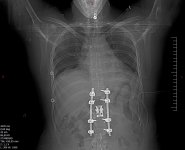

I broke my spine, had two surgeries (T12 arthrodesis), had to relearn how to walk again because I couldn't move my legs after the crash...